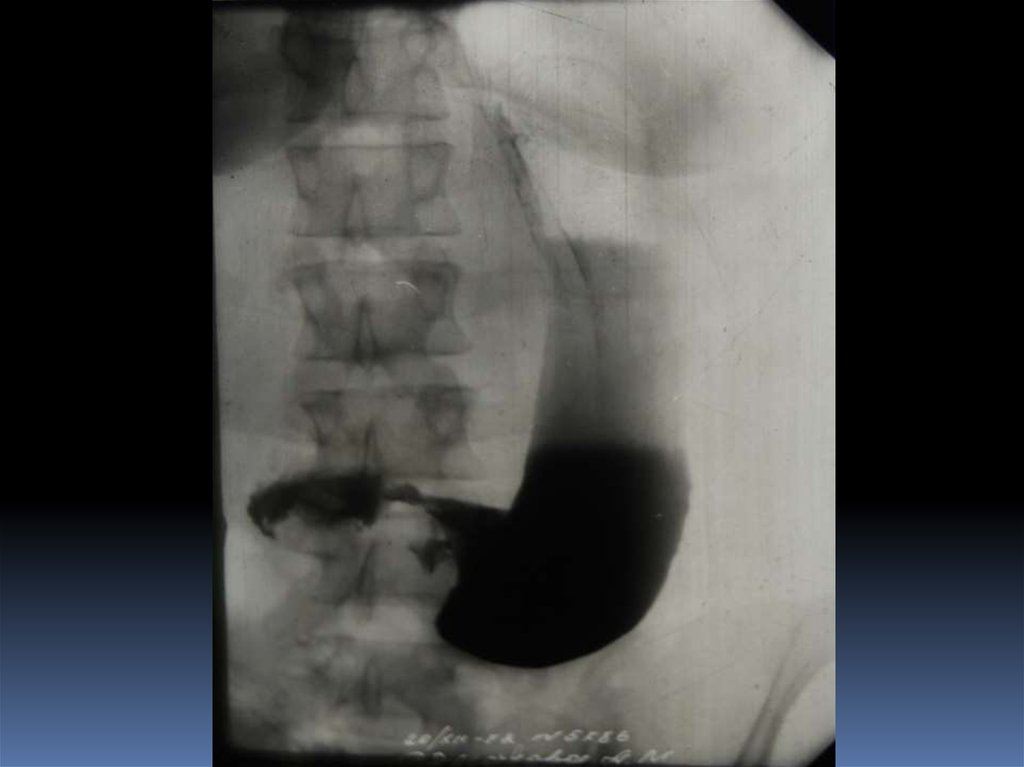

16. Рентгенодиагностика рака желудочно-кишечного тракта

Рентгенодиагностика

рака желудочнокишечного тракта